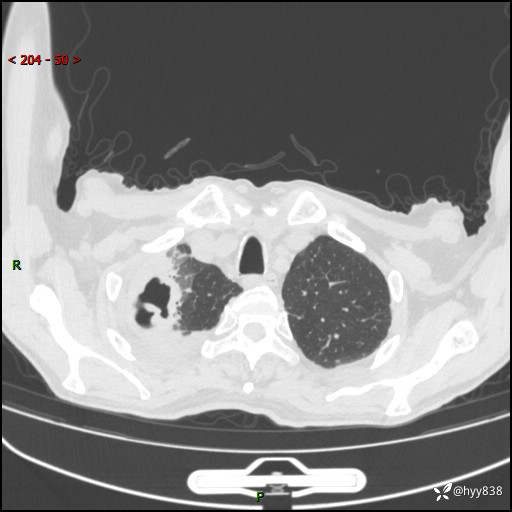

一个月后第二次CT检查(常规抗感染,患者不配合:增强、住院---)